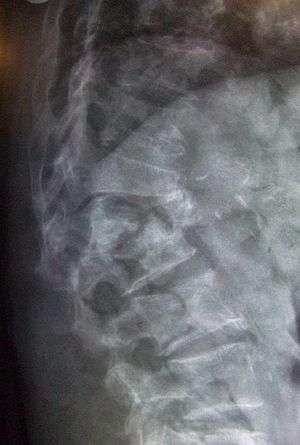

Lateral spine X-ray showing osteoporotic wedge fractures of L1/2.